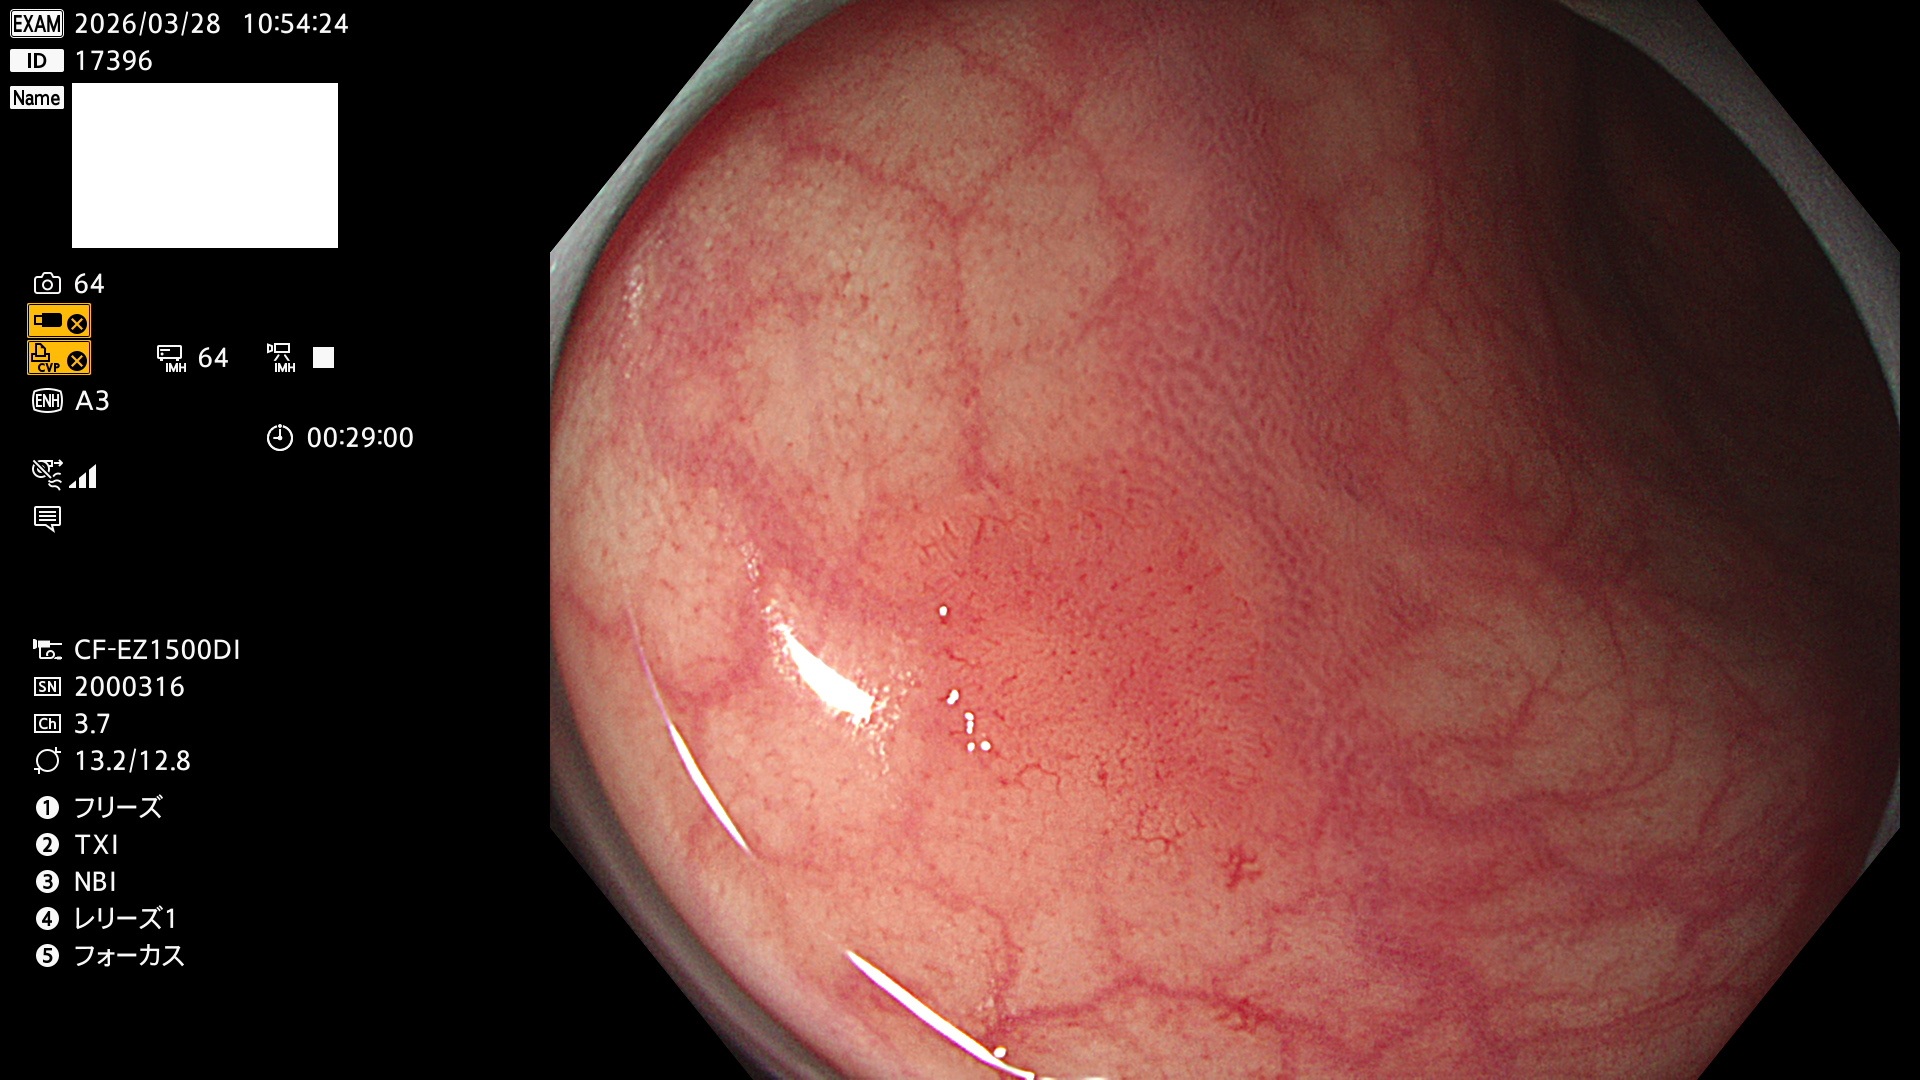

完全に平坦な物をUb、陥凹している物をUcと呼びます。Ubは認識が困難で、Ucはびらん(炎症)と紛らわしいために見落とされやすく、「内視鏡後・大腸癌」の原因になります。

専門的)Uc=De Novo癌? 内視鏡の解像度が低かった時代、このような説もありました。しかし今日の高精度内視鏡では良性の微小なUc型腺腫(APC遺伝子異常の腺腫)が日常的に見つかります。Ucこそが多段階発癌(Adenoma-Carcinoma Sequence)のMain Routeです。

毎週の検査(木・金・土・日)に発見されたUbとUc型・腺腫を、その週の日曜の夜にUPし1週間、提示します。

2026年3月26日〜3月29日の4日間(40件)4個 (Uc_ADR=4個/40人=10%)